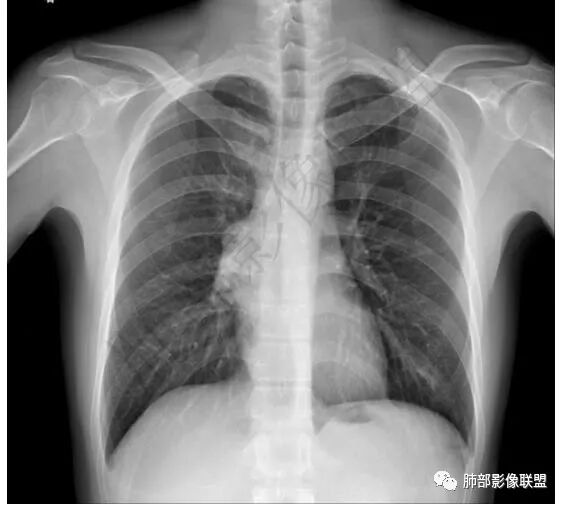

青年男性,咳嗽,右上前纵隔不规则肿块,分叶,上腔静脉受压,内乳动脉增粗,延迟强化明显,坏死不明显,考虑来源纵隔,胸腺瘤,淋巴瘤,神经源性肿瘤都可以,比较年轻,猜个淋巴瘤吧。神经源性肿瘤代排。

青年男性,前纵隔偏右侧肿块,分叶,与邻近血管分界不清,上腔静脉受压,不均匀渐进强化,点状坏死,考虑胸腺瘤,鉴别胸腺类癌

前纵隔肿块,轻度分叶,边界不清楚,延迟强化,可见分隔,倾向恶性或具有一定侵袭性病灶。